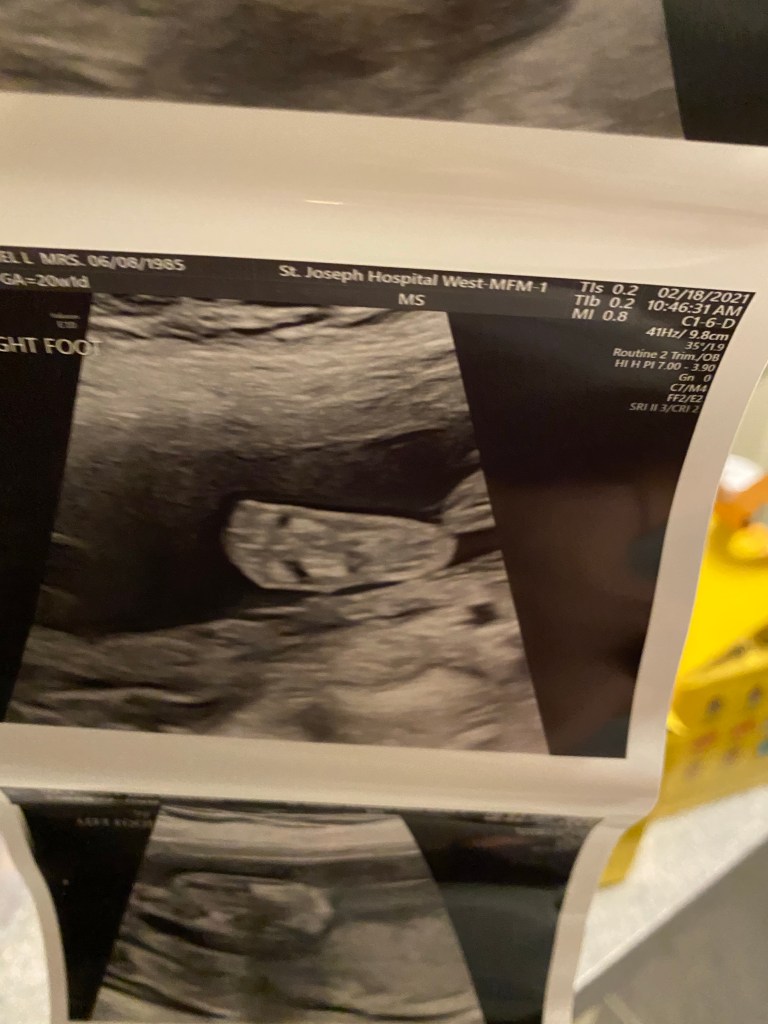

Today was the 20 week ultrasound at the MFM office at the hospital because now at 36 I’m an old pregnant lady. 😂 It was a long appointment and they looked at everything. We got mostly great news. He looks so perfect in there. He has sweet little lips and loves to move his arms and legs. I loved watching him wiggle around. He started out head down and we all know that makes me happy! But then he went transverse and then to breach! 😆 Obviously it’s still super early and he has lots of wiggle room to flip and turn and play. We could see all 4 chambers of the heart and his brain and spine they even looked at kidneys and eyes! Every square inch of this sweet boy we saw. The nurse practitioner did come in and let us know that it looks like we only have a two vessel umbilical cord. She said they normally have 3. The good news is because everything else seems perfect she said we shouldn’t really be worried. I will have to now have more appointments to watch and monitor his growth. So I will be going back every 4 weeks for a growth scan. The obvious perk is we will get to see his sweet little face more often!!! It will always amaze me how fast they grow and how perfect he looks. The screen makes him look SO big but in reality he was a whopping 12oz! A whole soda can in there. Seeing him wiggle and grow makes me love him even more and I can’t wait to see his sweet little face in 20ish weeks. Leaf was so sweet on the phone and talked about his baby brother coming. It’s so special to help a family have a baby but, it’s also so exciting to help make Leaf a big brother!!! I’m sure like any older sibling he’s going to be shocked that a new baby is there and all his normal attention has to be shared now but I just know he’s going to do great.